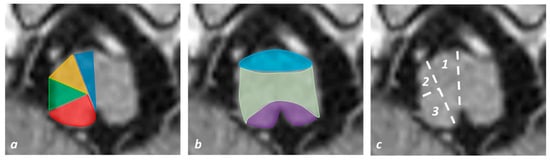

3.2. Pontine Infarction

3.3. Midbrain Infarction